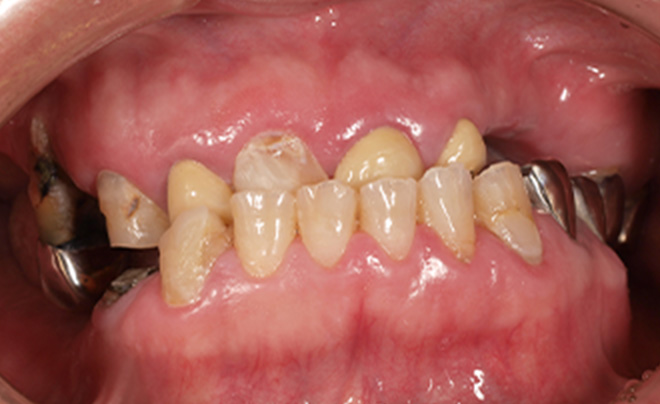

Before

After

| 55歳 男性 | |

|---|---|

| 主訴 | 前歯でしか咬めなく、食事を摂るのに非常に困難で辛い |

| 処置内容 | 上顎6本、下顎3本 |

| 治療費用 | 上顎: 約230万(税込) 下顎: 約120万(税込) |

| 治療期間 | 上顎: 1年(仮歯まで8ヶ月) 下顎: 8ヶ月(仮歯まで5ヶ月) |

| リスク | 上部構造物、仮歯の破折、術後の腫れ(3日)、人工歯根脱落リスクがあります |